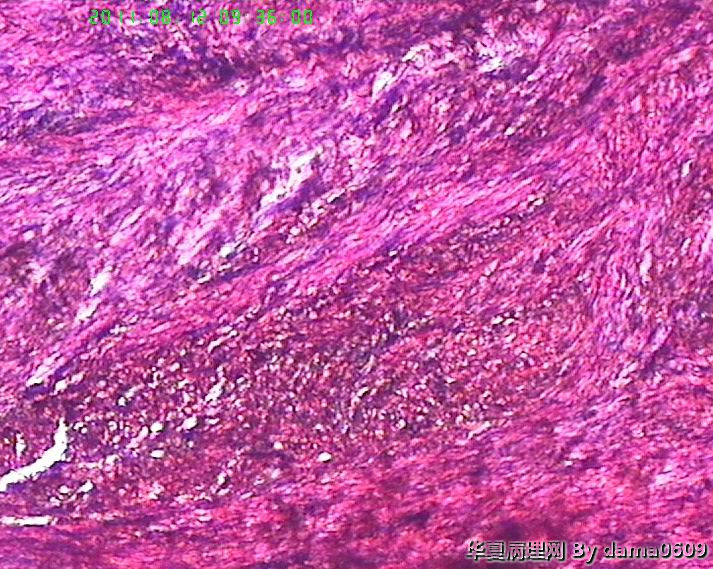

老师好!以前学生也遇到过此情况,偶尔染出的片子的细胞核的上方会出现黑色的异物,多见于子宫平滑肌瘤的片子。很影响观察核的形态、核分裂像。初以为是苏木素杂质,而且不经常出现,所以没在意。最近此现象很严重,许多的片子都出现此情况,反复过滤苏木素不见好转,新配苏木素也是如此。经过仔细观察,现发现似乎不是杂质,是细胞核上方覆盖着小气泡(如图),不知何故,如何解决??另外一个问题,我们的片子封片后经常出现斑片状或整张片子模糊,似乎树胶没有封到(如图),不只是脱蜡不干净,还是脱水出问题?此想象并不是出现在所有的一批片子上,而是个别。请老师们帮助指点。谢谢。